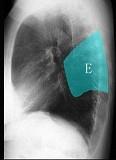

问题 如图所示正常胸部X线影像图像上,该英文字母所代表的肺段为 ( )

选项 A.内基底段 B.前基底段 C.外基底段 D.后基底段 E.背段

答案 E